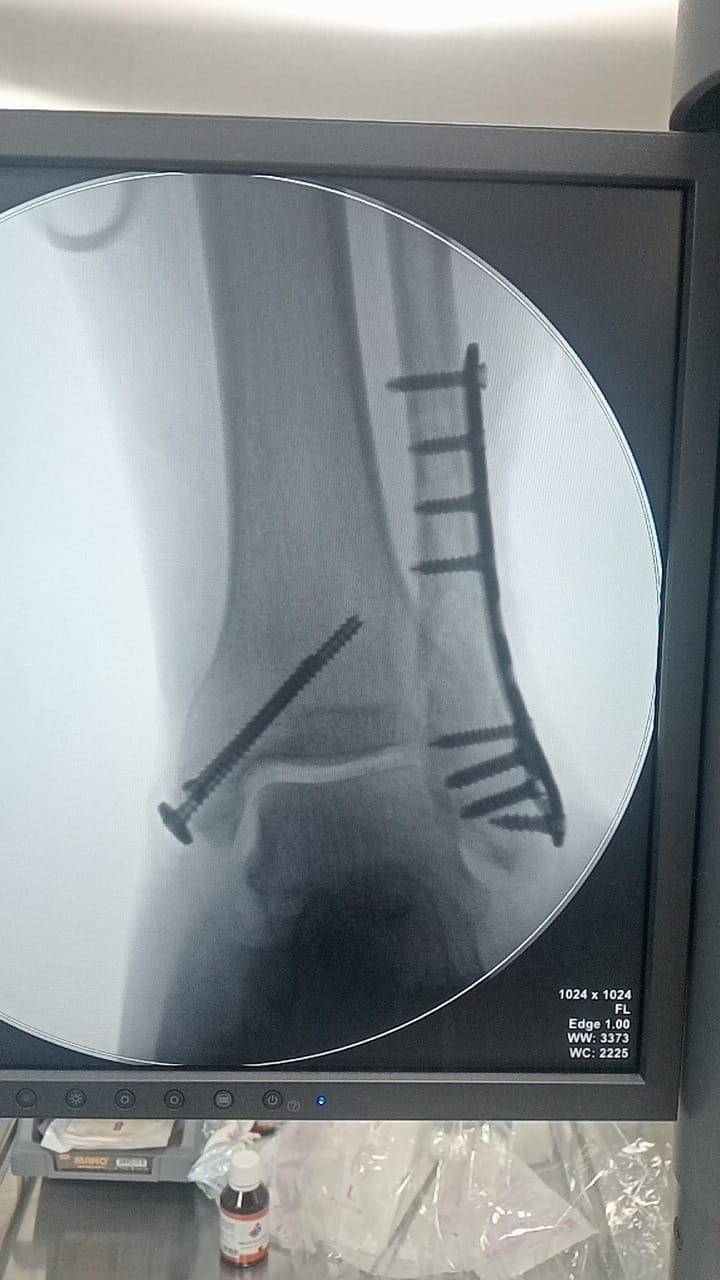

- إجراء عمليات جراحية معقدة و دقيقة في مجال العظام و المفاصل و الكسور و الإصابات ، رغم الضغط الكبير على المستشفى و أعداد المراجعين الكبيرة.

- تطبيق تقنيات جراحية حديثة و متقدمة، و ذلك في ظل التحديات التي يواجهها الفريق بسبب أعداد المرضى و المراجعين الكبيرة.